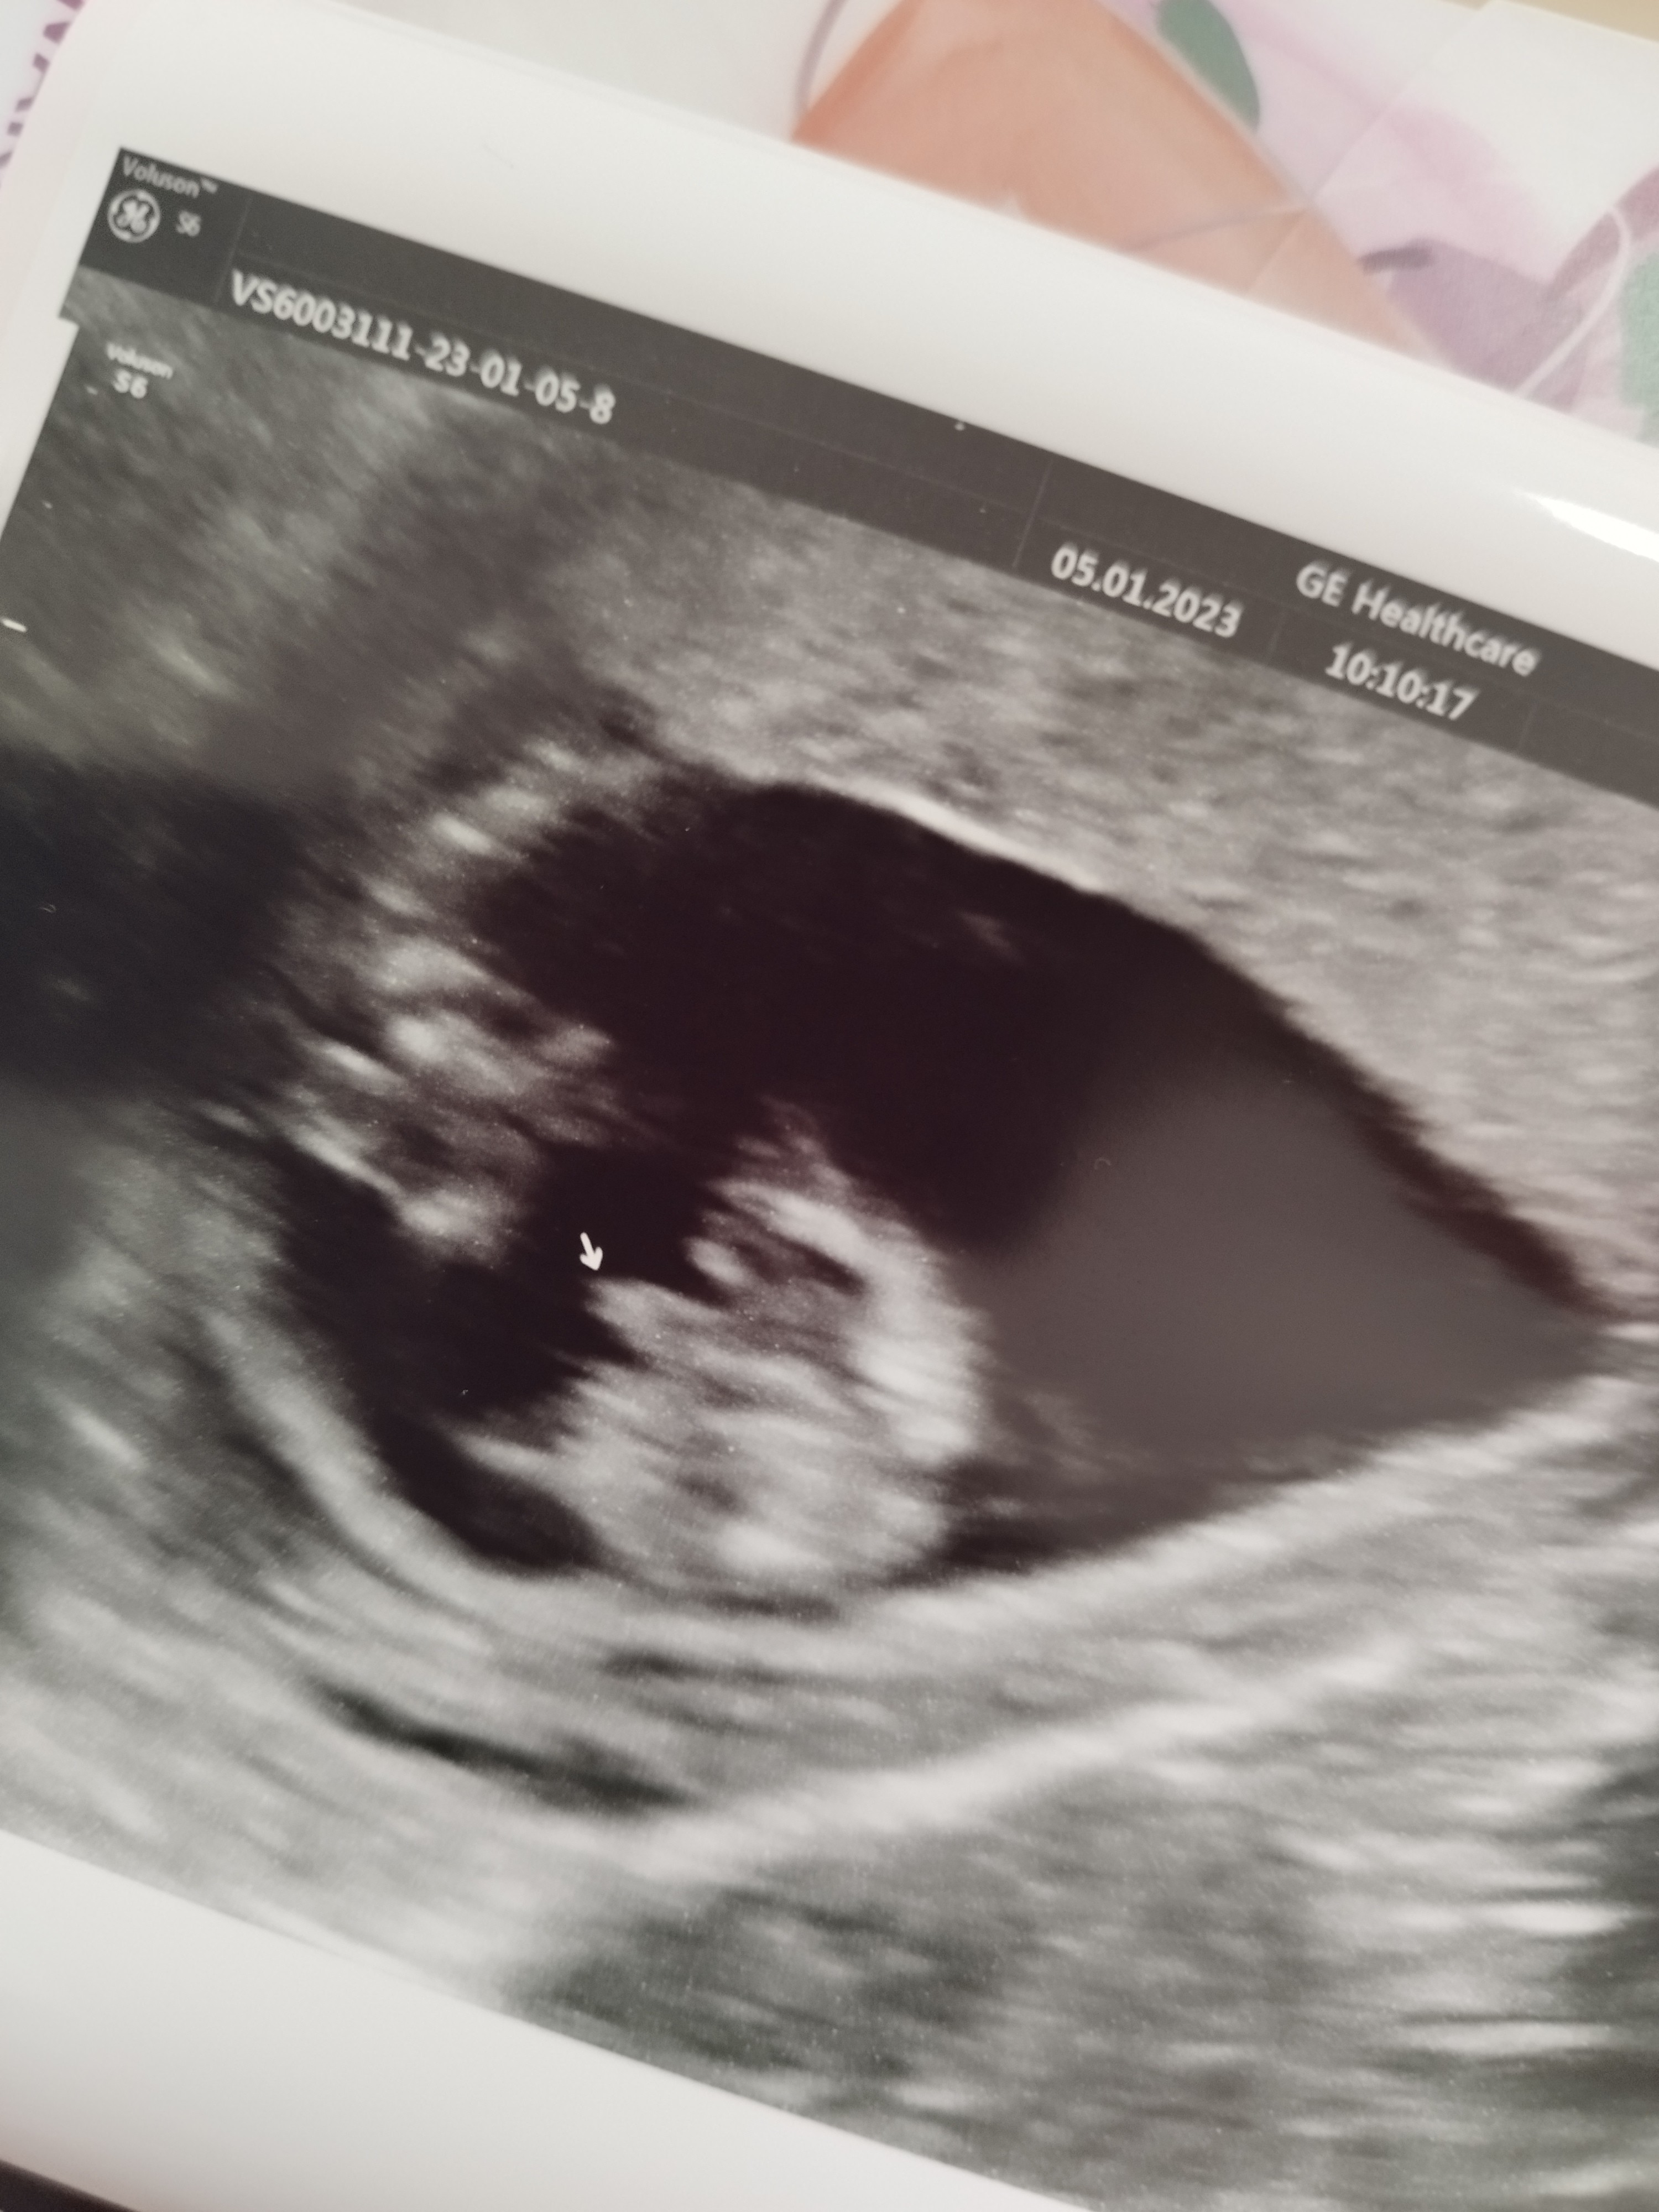

GratulujęAaaaa Na 90% chłopczyk , zdrowy jak rybakamień , serca

jutro jeszcze badania u mojego lekarza ale jest wszystko dobrze

jestem spokojna

Boże jestem najszczęśliwszą na świecie![]()

Jak zaczniesz czuć ruchy dziecka to dopiero będzie "dziwnie"Oj tak jak mówisz , koniec że stresemna chwilę mogę odetchnąć ...

A tak naprawdę to po mału zaczyna do mnie dochodzić że to się dzieje naprawdę . Nigdy ale to nigdy nie sądziłam że będę ma takim etapie , że będę w ciąży , będę nosić nowe życie pod sercem ... A to się dzieje